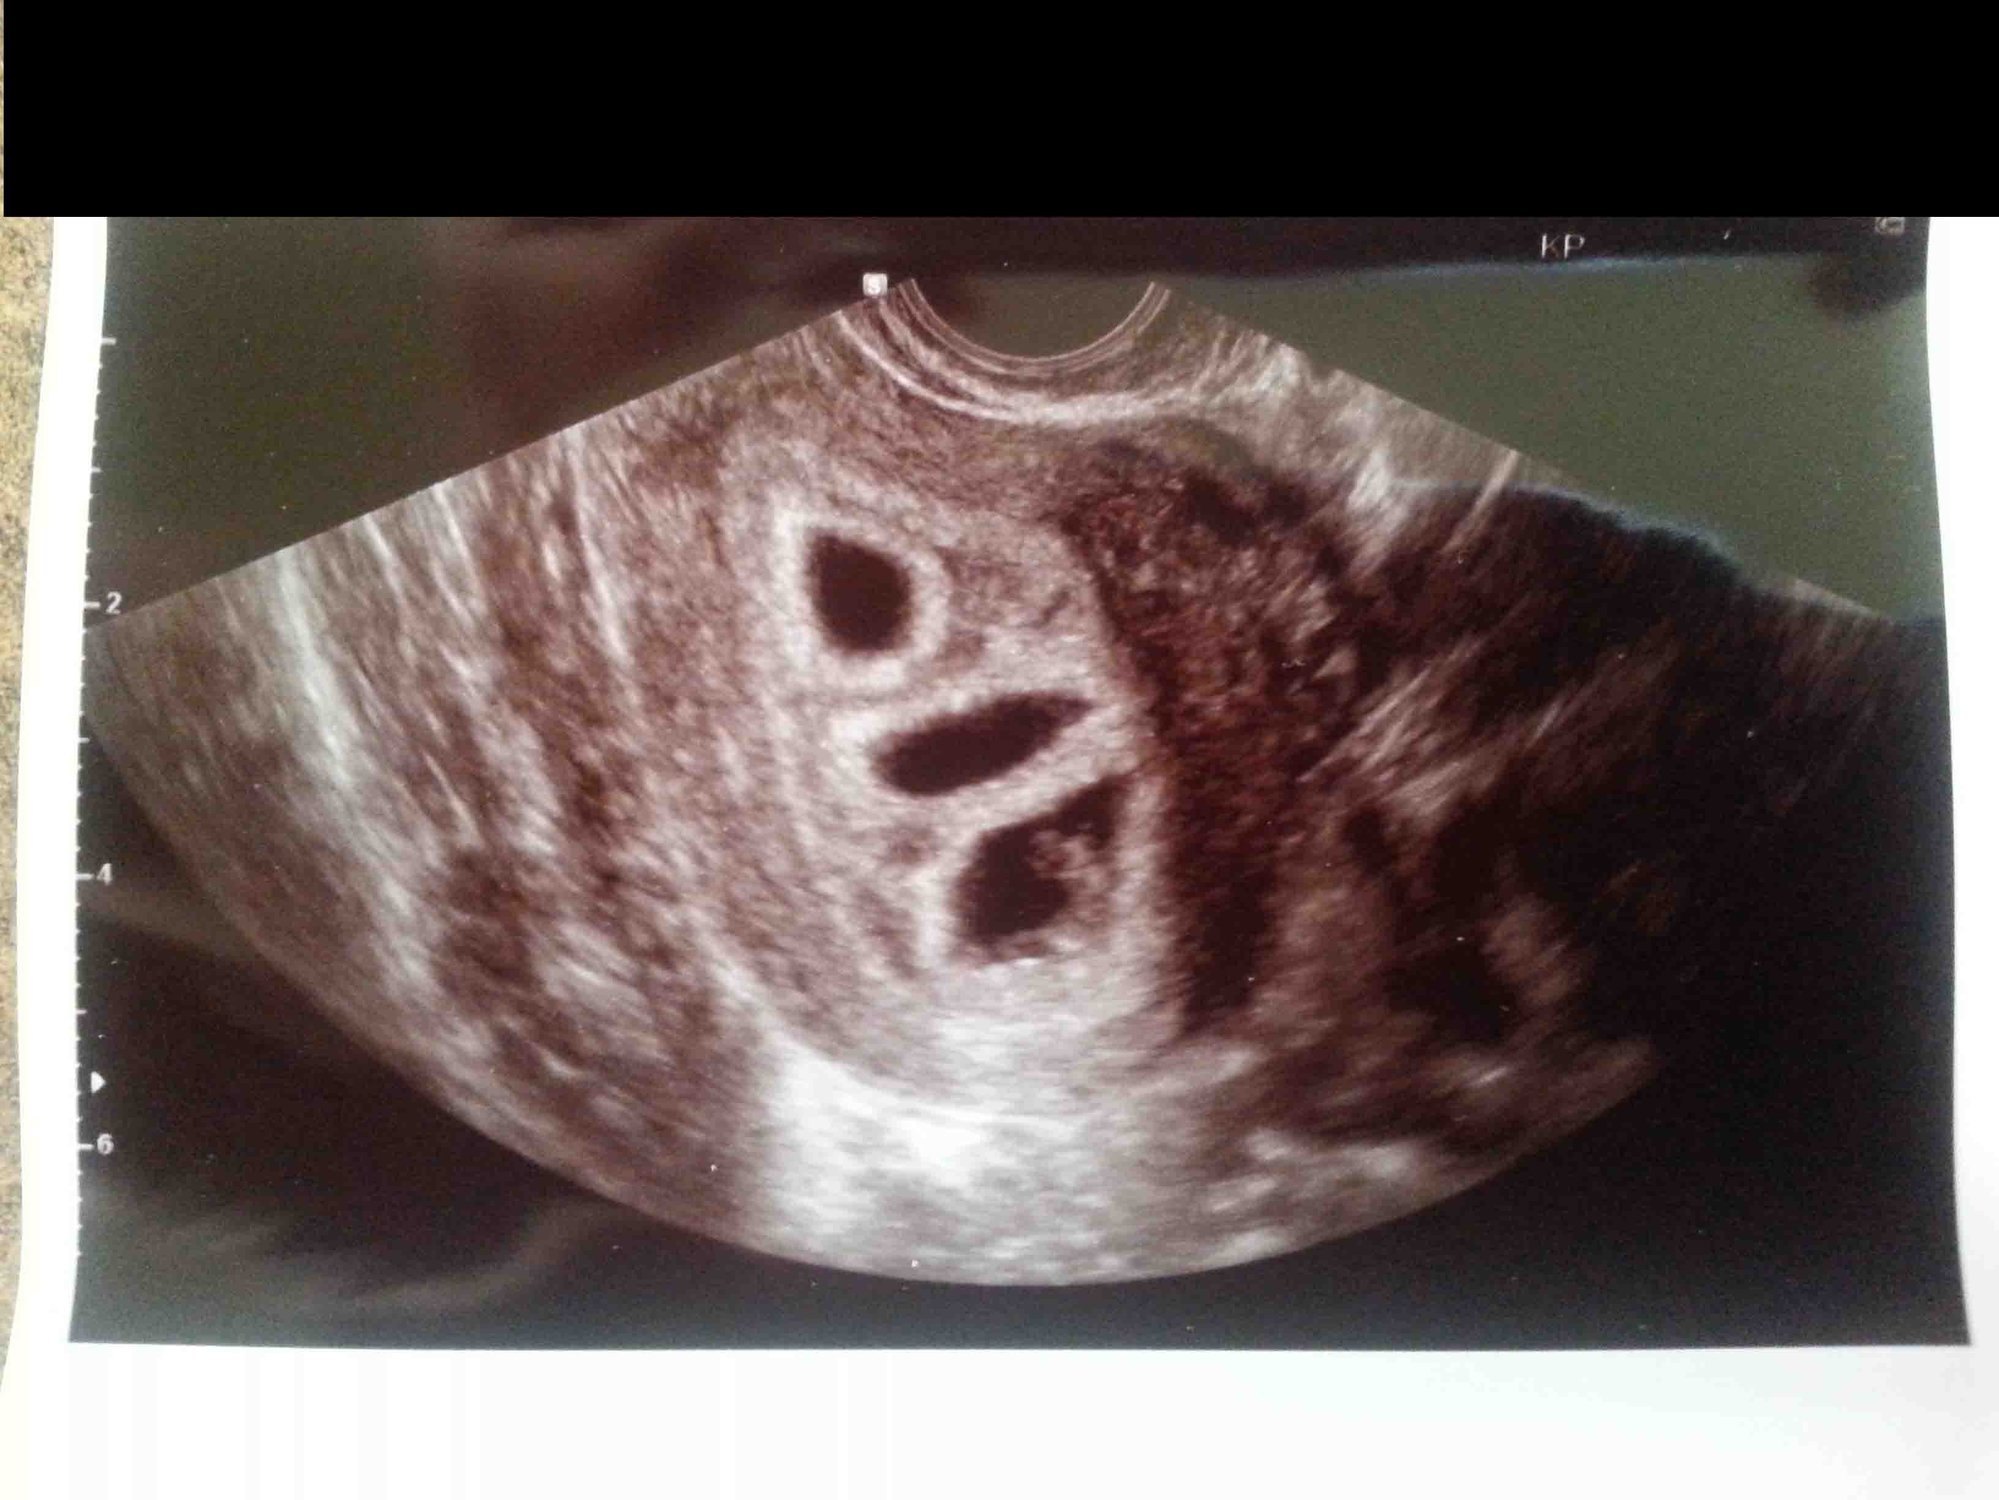

update: since I get to go to the doctor every 1-2 weeks, this is from last Friday.

this is from the high risk obgyn with the better ultrasound machine. good news. she thinks they are monodi but will confirm again in a few weeks

although she is measuring them to be smaller than LMP. by 5-7 days.. due date still in march, ill ask my regular obgyn what she thinks this Friday .

2 little nuggets. good heart rates

147 and 153